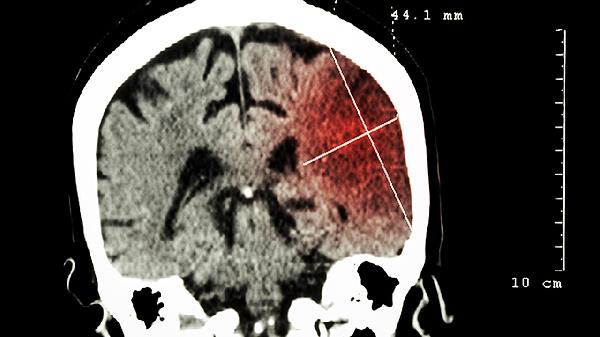

当宝宝出现持续呕吐、瞳孔不等大或抽搐时,需立即进行CT或核磁共振检查。影像学可明确是否存在颅骨线性骨折、蛛网膜下腔出血等问题。急诊科医生会评估格拉斯哥昏迷量表分数,必要时收治入院监测生命体征。

严重颅骨凹陷性骨折需行颅骨复位术,急性硬膜外血肿超过30毫升时实施开颅血肿清除术。术后需在PICU监测72小时,通过腰椎穿刺释放血性脑脊液,并使用头孢曲松钠预防颅内感染。